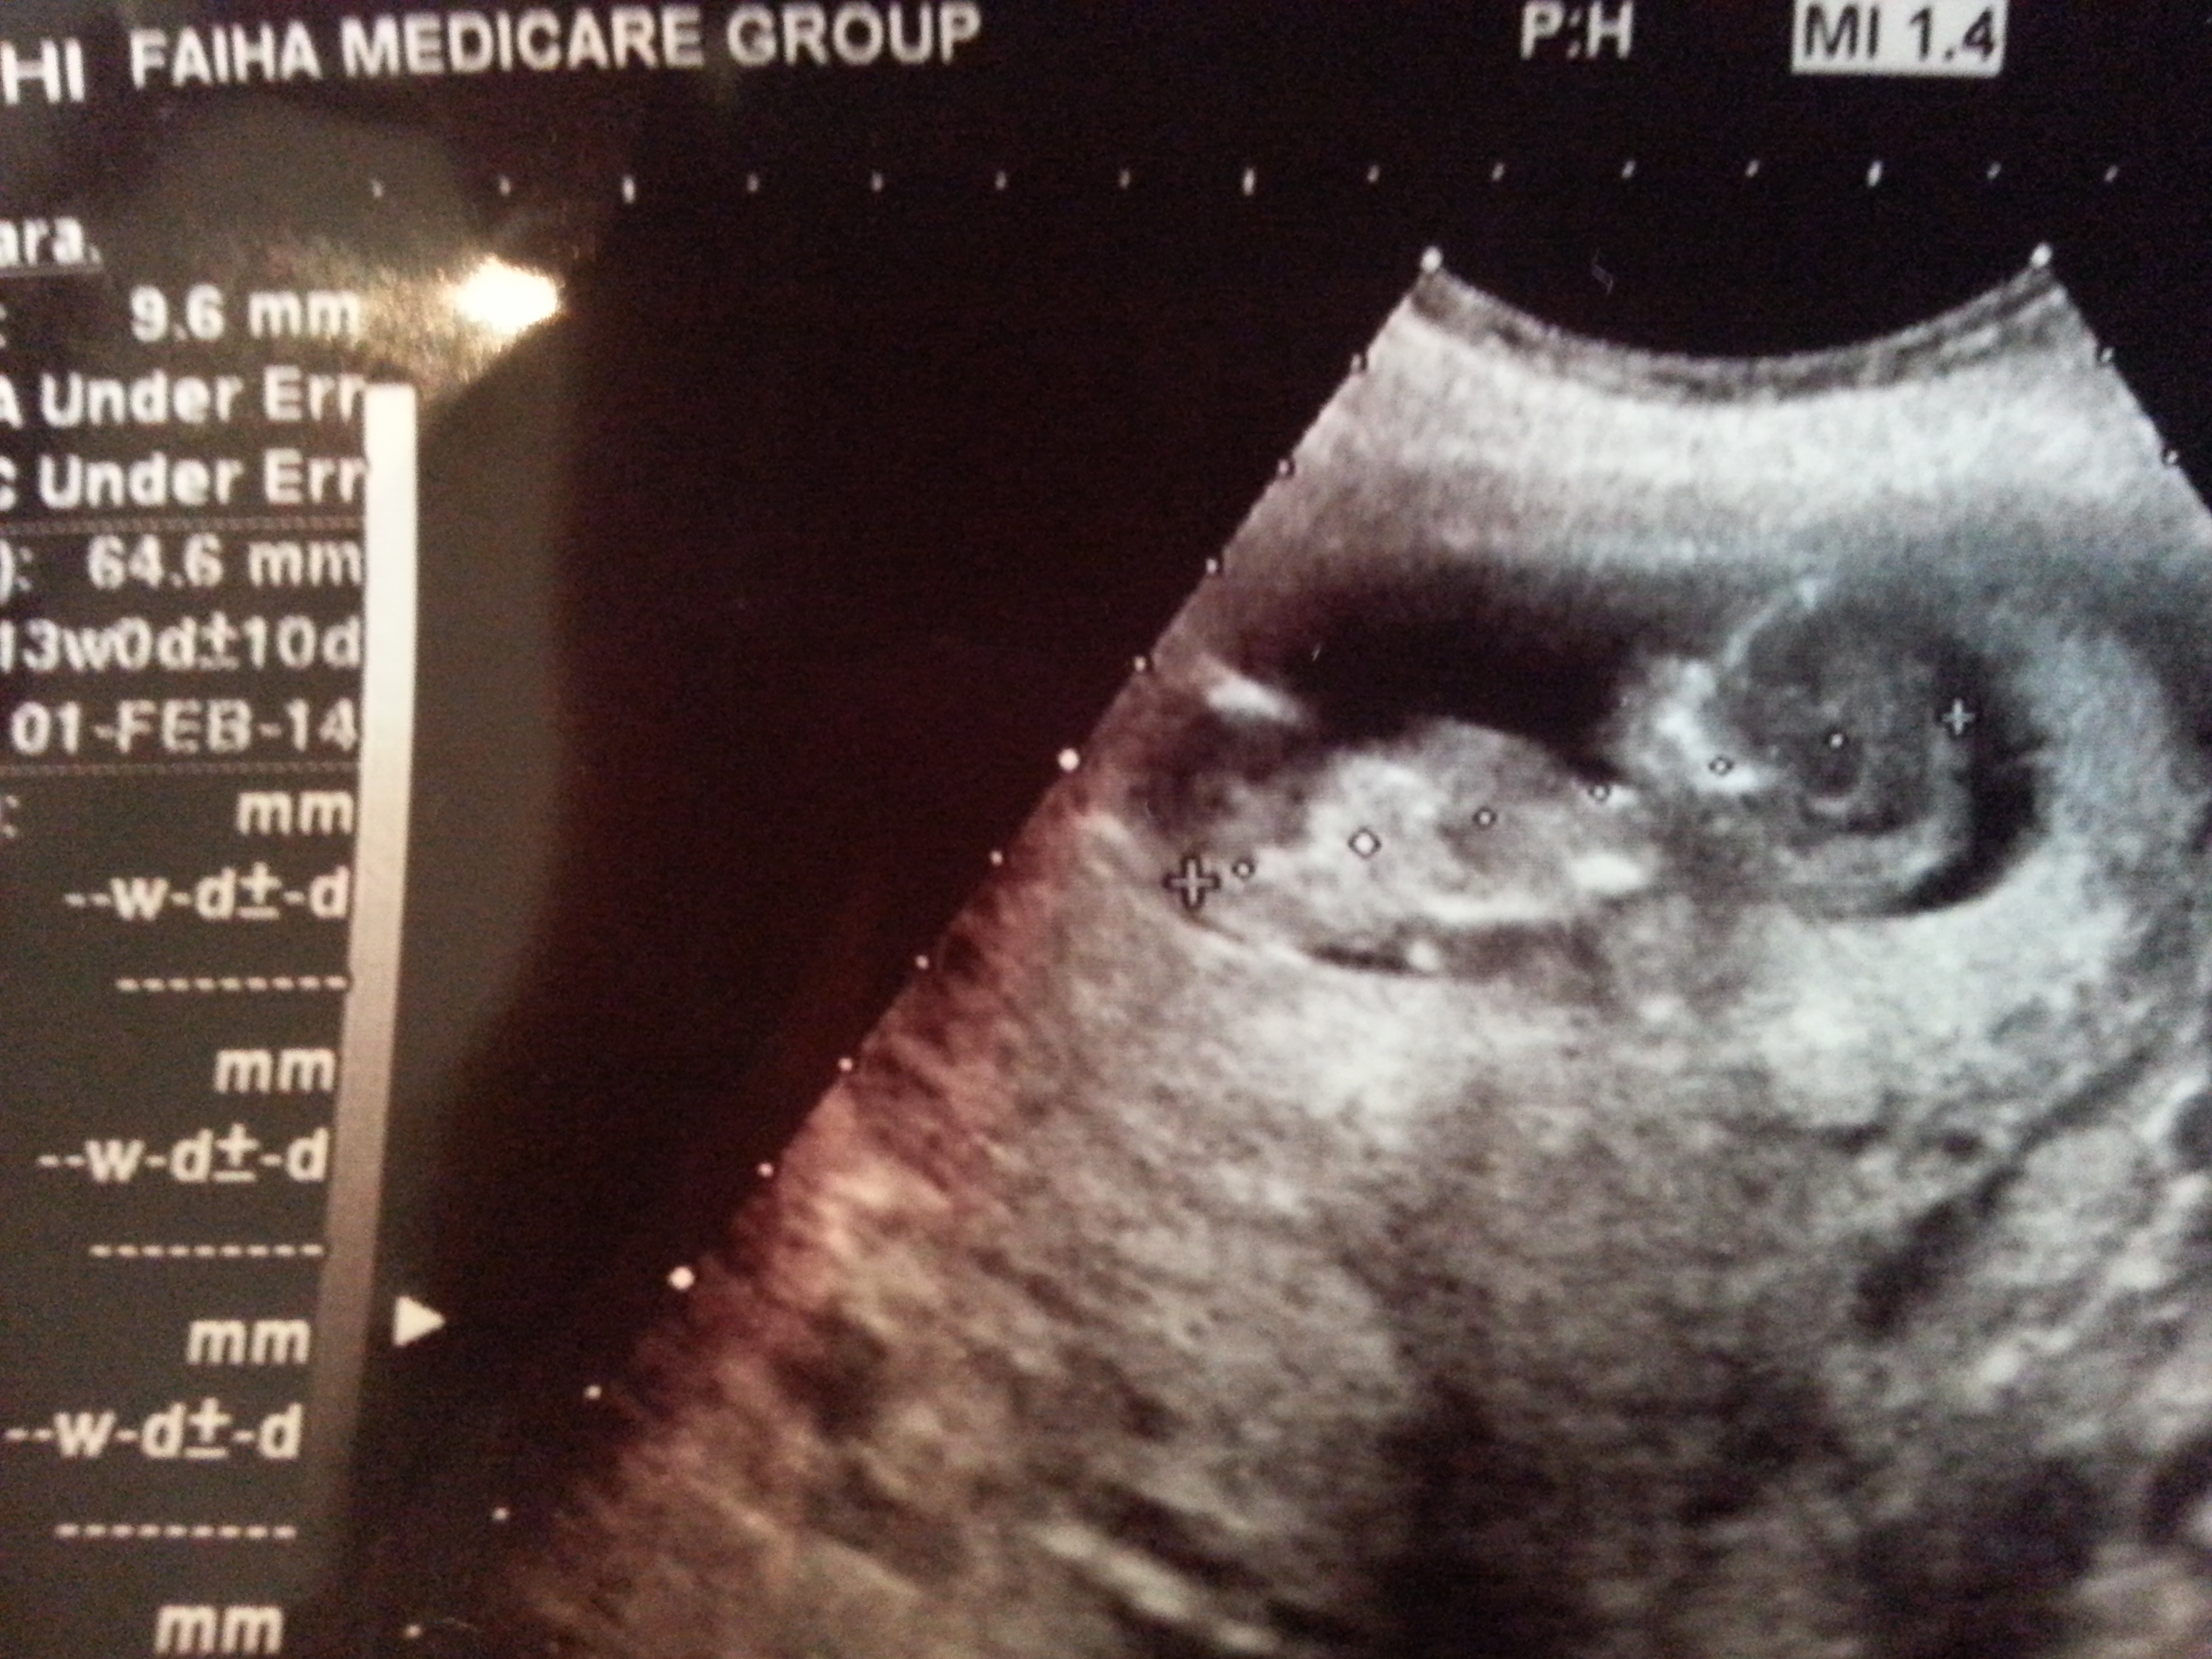

@ 12 week please guess nub or skull thoery please please Attachment 12610

There is something angled up on scan but not sure it's a nub. I will tentatively guess boy but wouldn't be surprised either way.

I think the skull looks boyish and if that is a nub it looks boyish too. Good luck

Looks to be something angled there but so little detail!! I guess boy aswell:) Any other pics??

I am also leaning boy. But it's hard to tell if that is the nub because of the lack of focus.